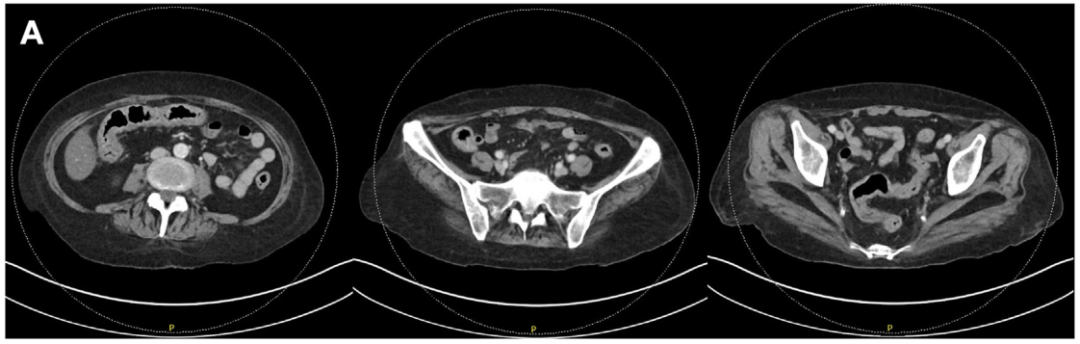

- 消化性溃疡怎么治?除了抑酸,这些诊治细节不容忽视!|图表总结要点 为帮助临床医师对PU进行准确、合理的诊断与治疗,《消化性溃疡中西医结合诊疗专家共识(2025年)》主要从中西医角度对PU的认识、诊断、治疗等方面入手,对PU中西医结合诊疗形成的主要观点进行总结,为临床提供参考。……